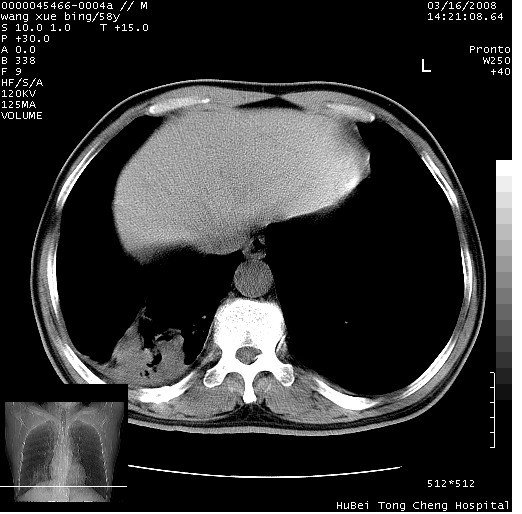

患者 男,58岁。咳嗽、咯血3月余。

胸部cr x线片提示:1)右下肺脓肿。2)右下肺周围型肺癌不排除。建议:行ct扫描检查。

胸部ct轴位平扫(层厚10mm,螺距1.5,重建间隔10mm),图像如下:

右肺下叶团块及不规则空洞,内壁不规则,外缘见粗长毛刺,临近胸膜明显增厚并与病灶关系密切。支持考虑:右肺肺脓肿!建议穿刺病理检查待除外周围型肺癌!

考虑右下肺周围型肺癌并远端阻塞性炎症及胸膜转移

考虑右下肺中心型肺癌并远端阻塞性炎症及胸膜及纵隔淋巴转移

影像符合癌性空洞表现,临床如无咳大量浓臭痰史,还是考虑周围型肺癌可能性大。